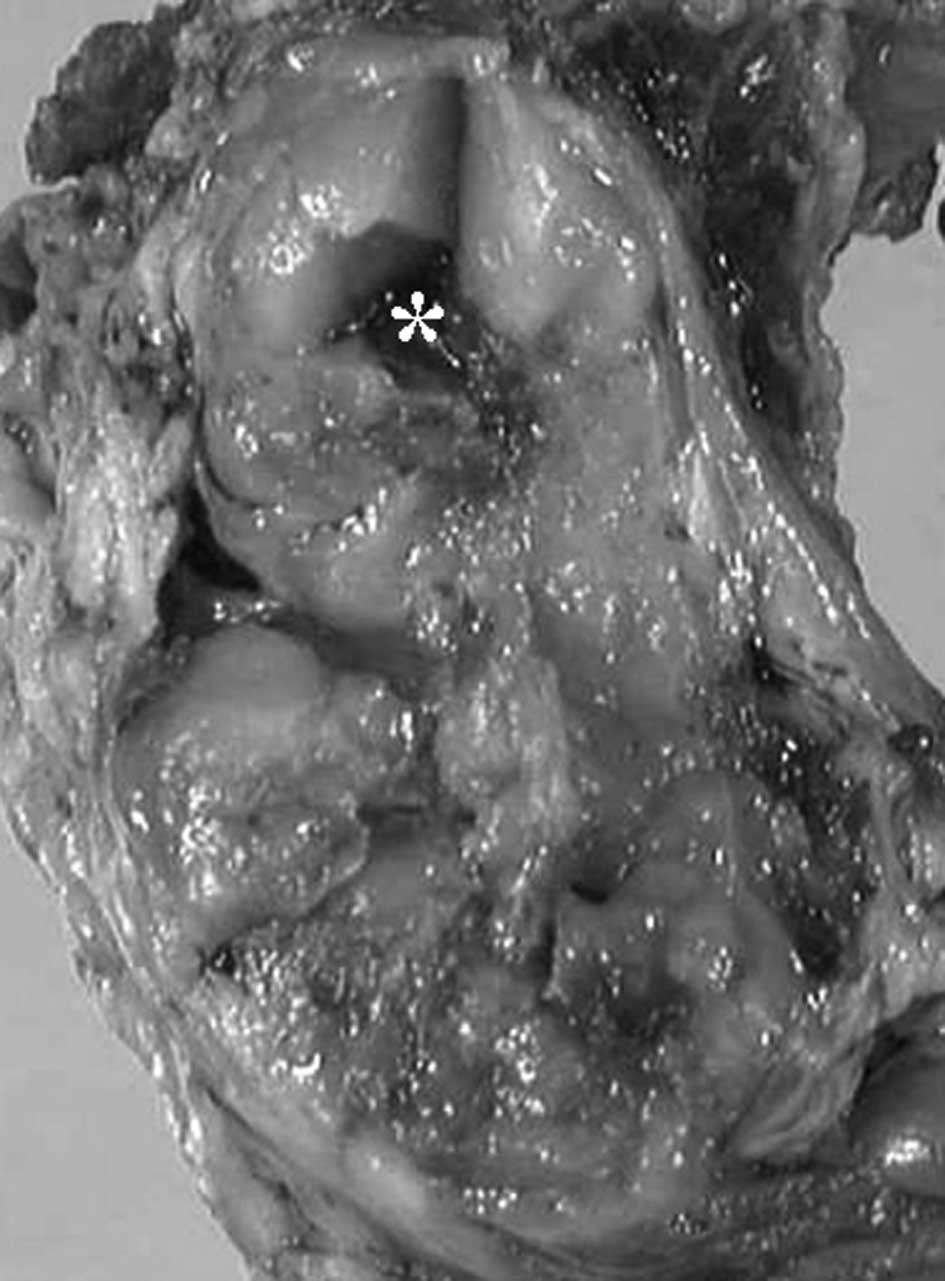

Extraskeletal myxoid chondrosarcoma of the thigh with a t(9;17) translocation

Extraskeletal myxoid chondrosarcomas (EMC) are relatively rare. We report a case of EMC of the thigh. A 41-year-old man presented with a tumor history of more than 4 months. Following open biopsy, wide resection of the tumor was performed. Histopathologically, the tumor had a multinodular architecture consisting of myxomatous areas demarcated by fibrous septa. Proliferation of uniform, round tumor cells with oval nuclei was observed. Well-formed hyaline cartilage and rhabdoid-like cells were not visible. Immunohistochemically, the tumor cells were positive for vimentin and S-100. The composite karyotype was 46,XY,t(9;17)(q22;q11),t(9;21)(q21;p13), and the diagnosis of EMC was made. No recurrence of the mass or metastasis was observed during a follow-up period of 4 years and 7 months. Only 50 cytogenetic cases of EMC, including our case, have been reported in the English literature thus far. Clinical presentation, radiological features and histopathological and cytogenetic findings are described, and the relevant literature is reviewed.

Figure 1